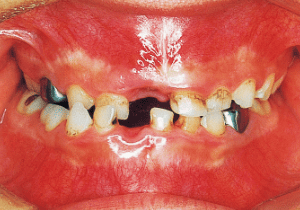

12 Before Phase 2 Treatment 10-26-’96 15 years 3 month

13 Before Phase 2 Treatment 10-26-’96

14 Before Phase 2 Treatment 11-6-’96

Although early treatment improved the slight deviation observed during the deciduous dentition stage, it became apparent that the deviation increased with age, eventually exceeding the limits of treatment. This appears to be an innate deviation, and the developmental pattern observed in this case seems to disregard the occlusion. Four first premolars were extracted (15), crowding was corrected and space closure was performed (16), and surgical intervention improved the deviation (17).